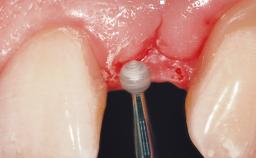

A 39-year-old male patient presented with a chief complaint of discomfort and gingival discoloration around his maxillary left central incisor. He was in good general health and was a non-smoker. His past dental history was significant because of the traumatic fracture of tooth 21 in a sporting accident at age 13. Initial dental treatment included endodontic therapy and a full-coverage restoration. The patient became symptomatic 5 years later, when structural failure of the tooth resulted in the dislodgment of the crown. Endodontic retreatment, apical surgery, and post-and-core restoration were performed.

Bone Augmentation Horizontal|Staged

Soft Tissue Grafting Simultaneous